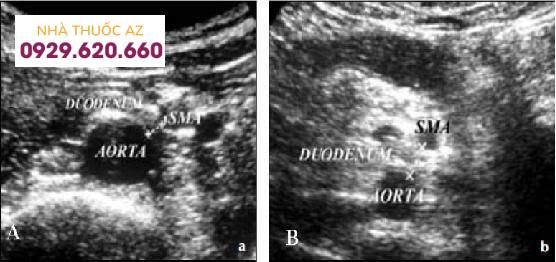

Đo khoảng cách giữa ĐMTTT và ĐM chủ bụng. A, đo được 3.8 mm. B, khoảng cách 9 mm. Nguồn : Birsen Unal et al. Superior mesenteric artery syndrome: CT and ultrasonography findings. Diagn Interv Radiol 2005; 11:91

Đo góc giữa ĐMTTT và ĐM chủ bụng. A, đo được 70. B, 320. Nguồn: Birsen Ünal et al. Superior mesenteric artery syndrome: CT and ultrasonography findings. Diagn Interv Radiol 2005; 11:91